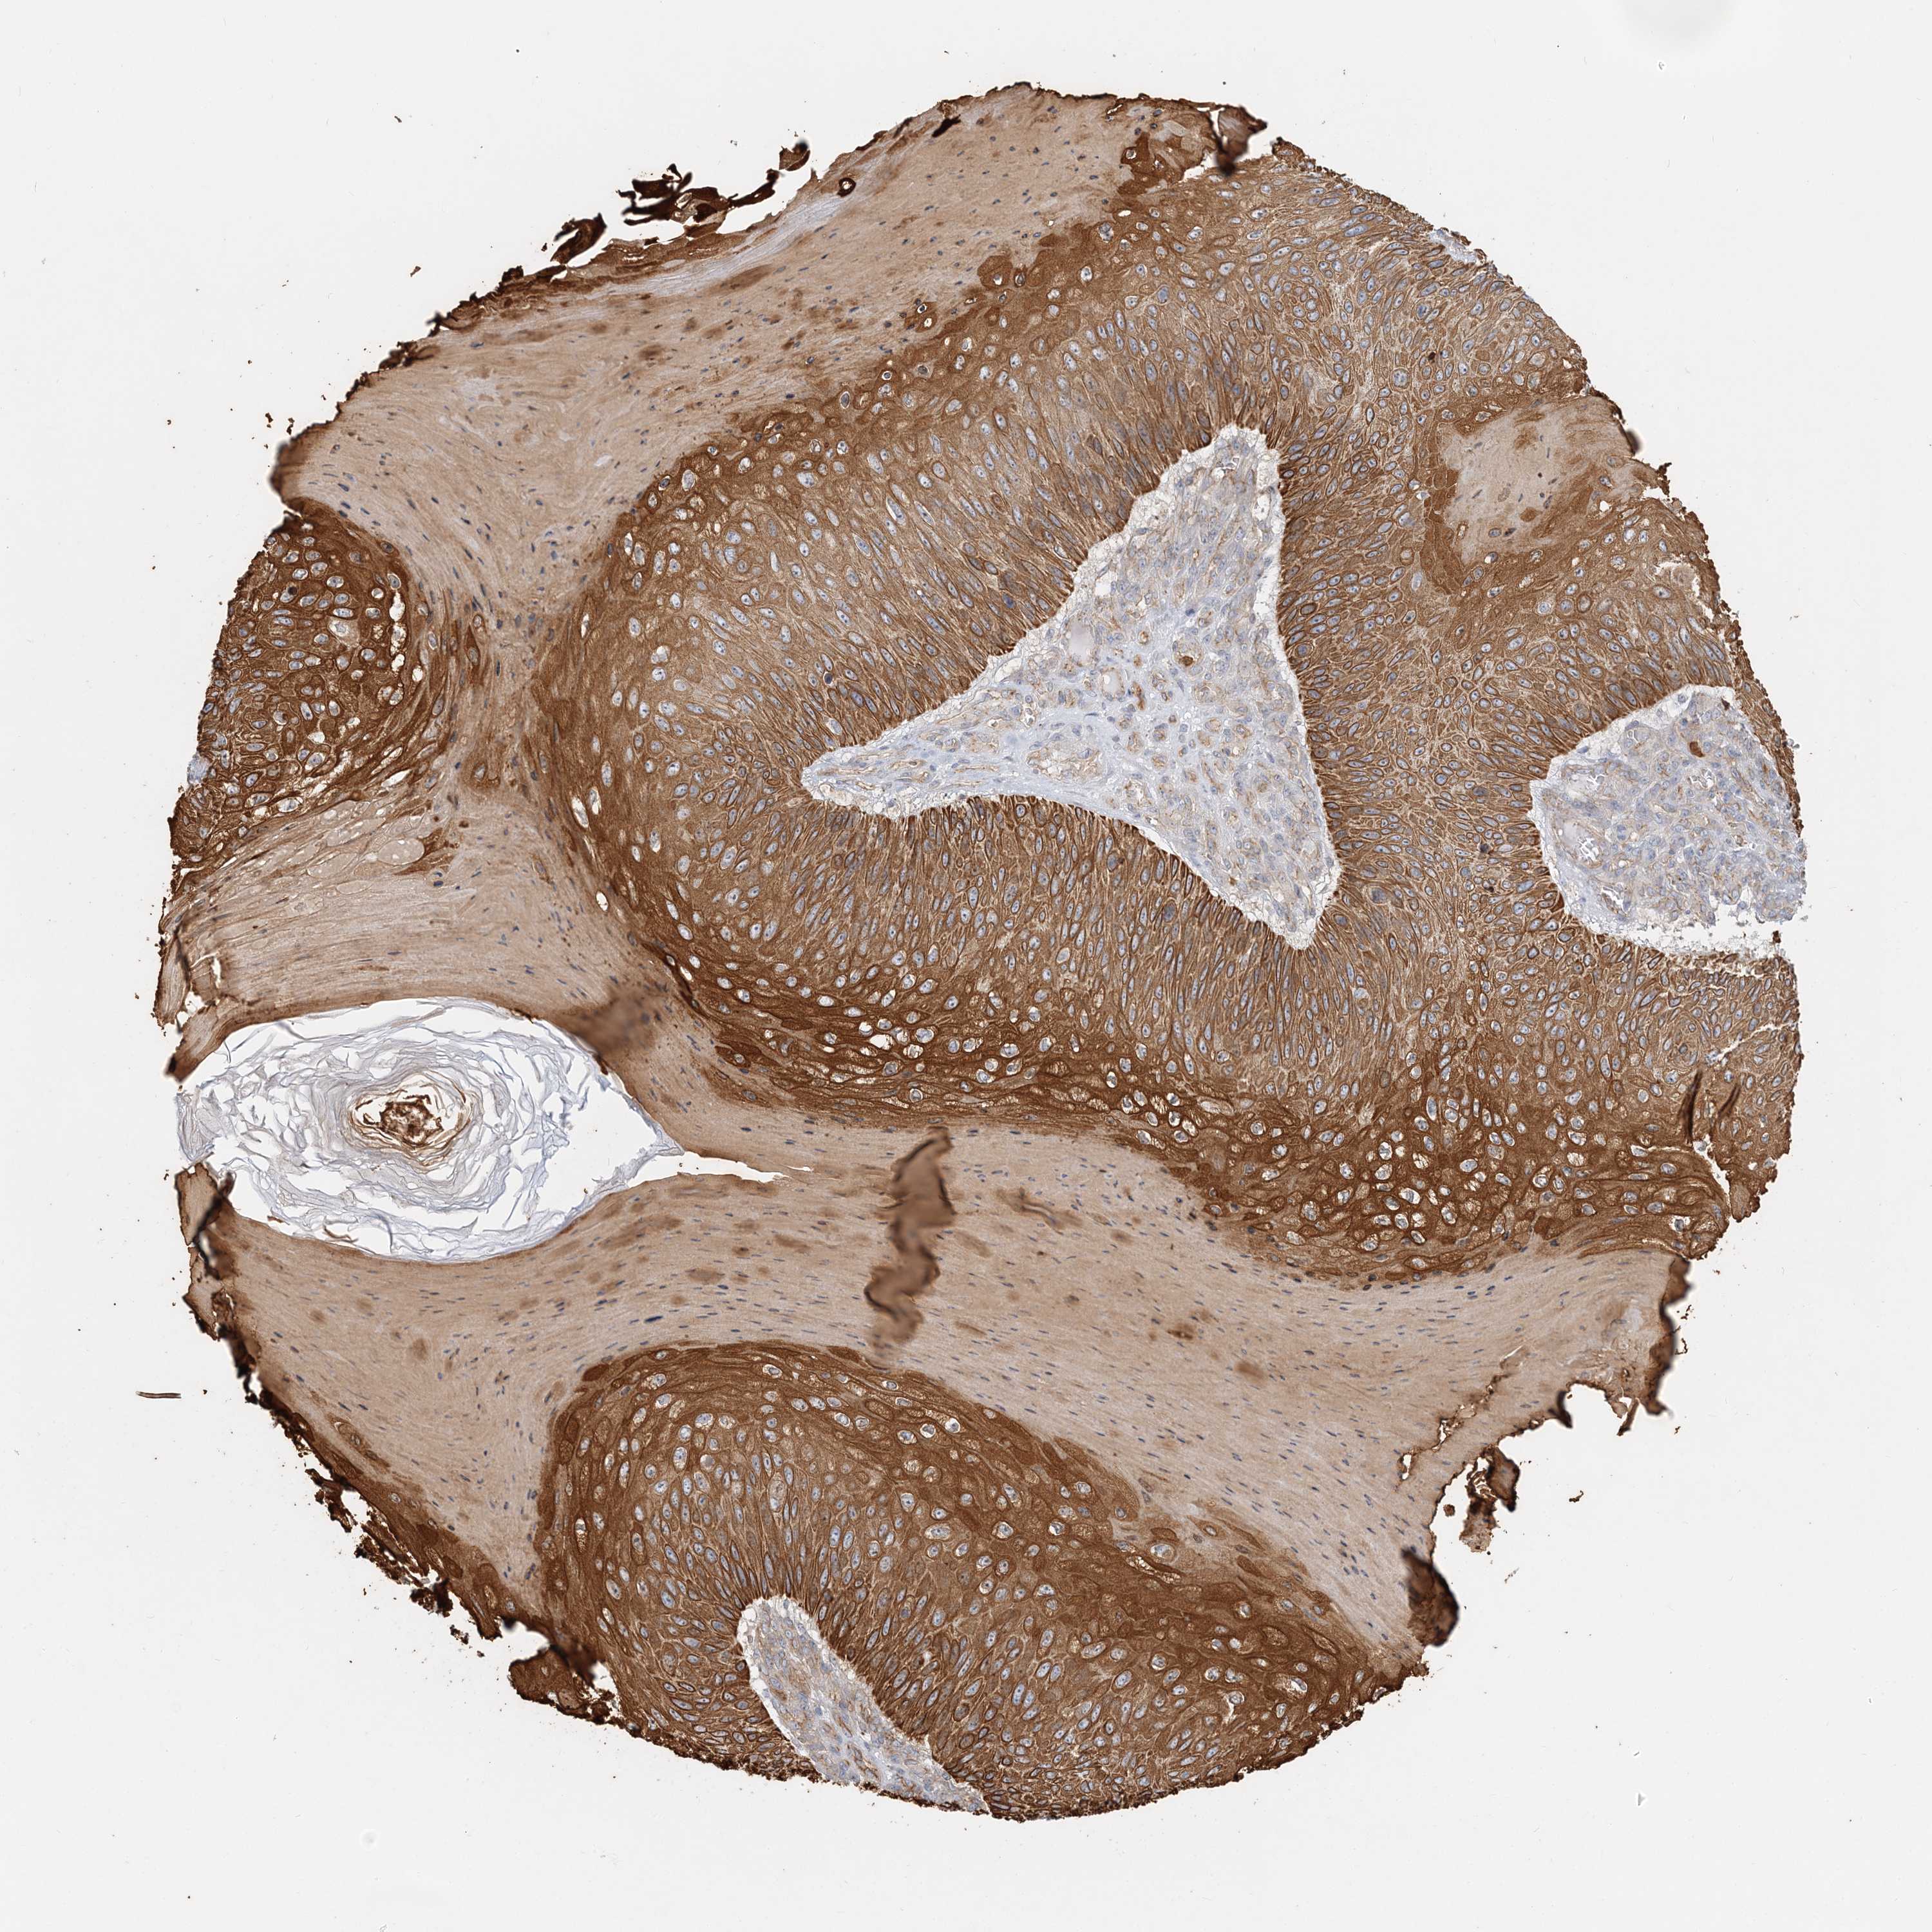

SKIN CANCER - Protein expressioni

A mouse-over function shows sample information and annotation data. Click on an image to view it in a full screen mode. Samples can be filtered based on level of antibody staining by selecting one or several of the following categories: high, medium, low and not detected. The assay and annotation is described here.

Each image is clickable and will lead to virtual microscopy that enables deeper exploration of all samples and also displays staining intensity scores, fraction scores and subcellular localization as well as patient and tissue information for each sample.

Antibody HPA036806

Squamous cell carcinoma, NOS